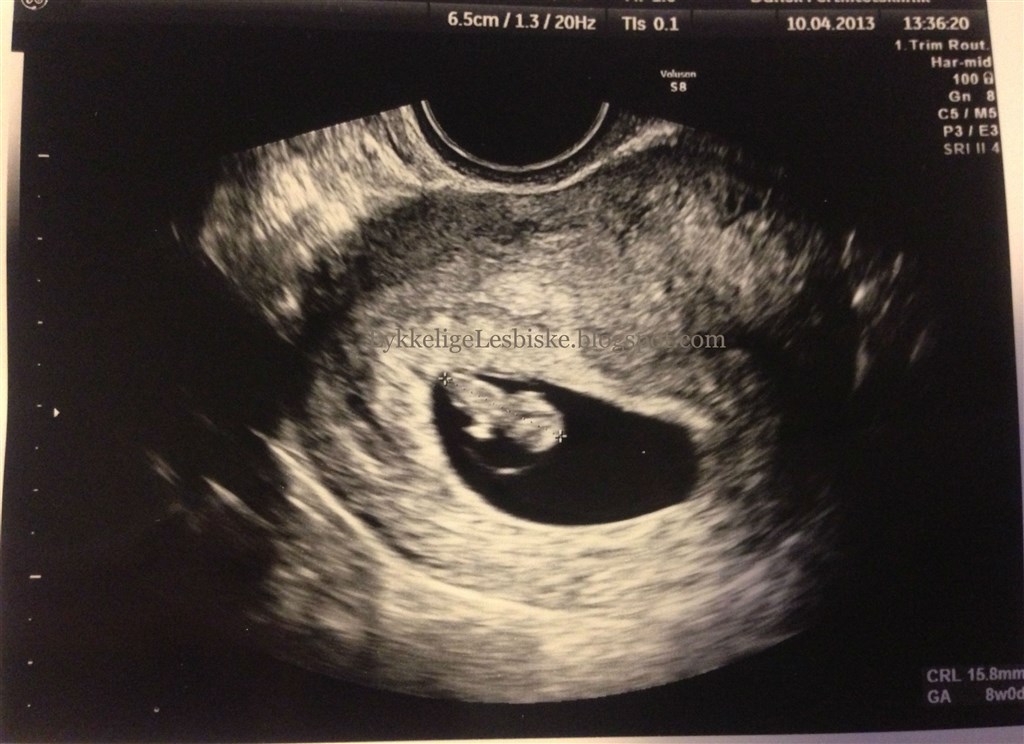

Jaaaa, så kom dagen endelig hvor vi skulle til vores første scanning!

Det gik bare så godt, ligeså snart scannings-pinden (ved ikke hvad jeg ellers skal kalde den.. den ligner mest en dildo

) kom ind kunne man straks se at der lå en lille baby

Vi er bare så lykkelige lige nu! Baby blev målt til 15,8 mm, så jeg blev rykket to dage frem og er altså 8 uger henne idag

Vedhæftede fotos (klik for at se i fuld størrelse)